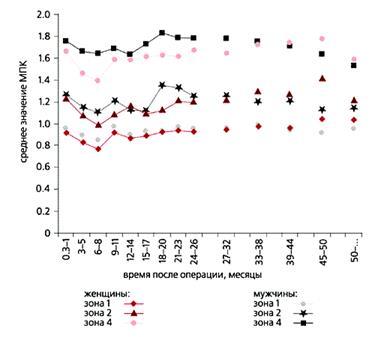

С помощью прибора было проведено около 1000 обследований более 100 пациентов в течение полутора лет. На рис.6 приведены результаты сравнения изменения минеральной плотности костной ткани в различных зонах вокруг эндопротеза у мужчин и женщин в зависимости от времени, прошедшего после операции. Видно, что потеря костной массы в первые месяцы после операции у женщин происходит интенсивнее, чем у мужчин. По мере накопления статистической информации будут получены новые данные о зависимости массы костной ткани от разных факторов, что позволит более эффективно использовать лекарственные препараты.

Рис. 6. Сравнение минеральной плотности костной ткани (МПК) в различных зонах шейки бедра вокруг эндопротеза у мужчин и женщин в зависимости от времени, прошедшего после операции.